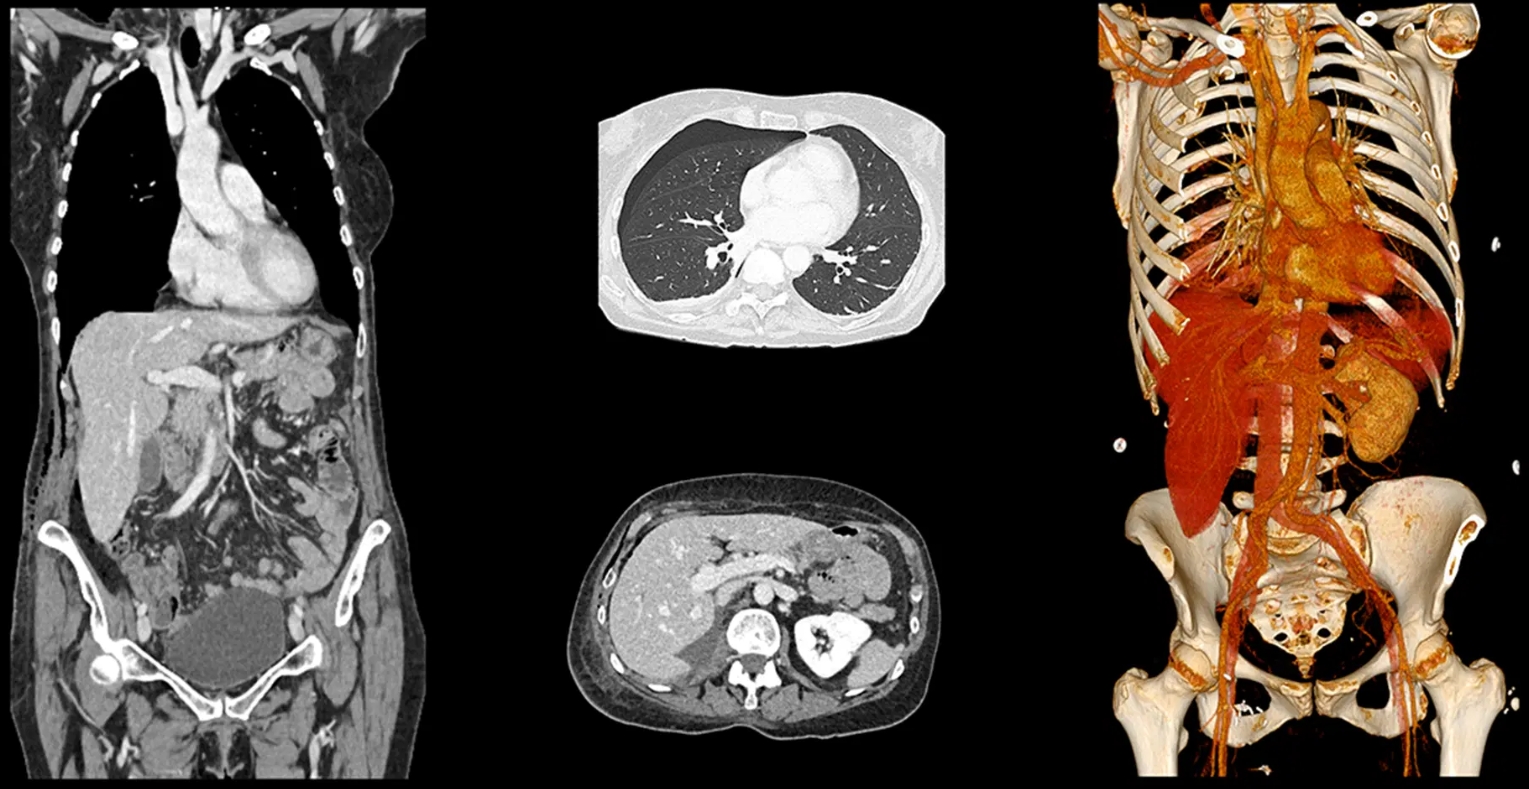

A Computed Tomography (CT) scan is an advanced imaging technique that uses X-ray technology to provide detailed cross-sectional images of the body.

These images allow healthcare professionals to visualize internal organs, blood vessels, bone and soft tissues in great detail, making them a valuable diagnostic tool for identifying various conditions and injuries.

- High-Quality Detailed Images: CT scans provide clear and detailed images of internal organs, soft tissues, bones, and blood vessels, making them superior to standard X-rays for diagnosing complex conditions.

- 3D Visualization: CT scans can create 3D images, enabling doctors to better visualize complex structures and plan surgeries or treatments more precisely.